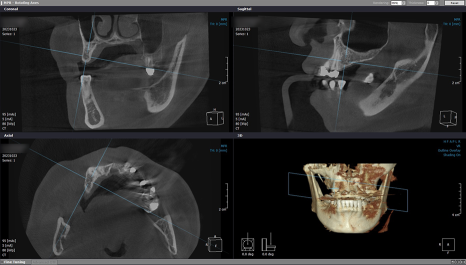

본격적인 치료 전,

픽스처를 심기 위한

치조골 위치를 정확히 파악하기 위해

3D-CT 촬영을 했으며

음식을 씹는 데 불편함이 없으시도록

좌측부터 인공치를 만들기로 했습니다.

환자분 뼈 상태의 해부학적 구조를

면밀하게 파악한 다음

잇몸뼈 높이와 폭, 각도 등을 고려해서

좌측부터 인공 치근을 심었습니다.